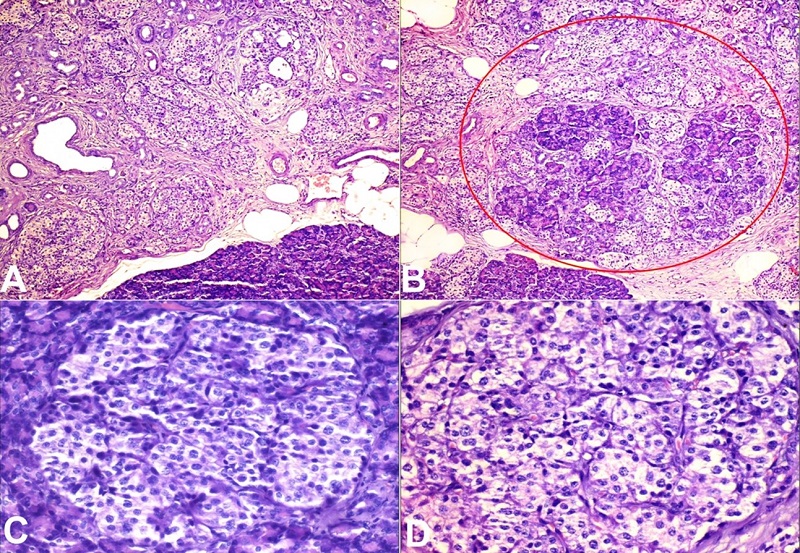

A frozen specimen of distal pancreatectomy was received at our laboratory and was proceeded for analysis. The specimen measured 7x5x1 cm, weighing 15 g. The outer surface and the parenchyma on the serial section were unremarkable. No definitive growth was identified. Microscopic examinations showed maintained lobular exocrine pancreatic parenchyma architecture, with a proliferation of islet cells arranged in variably sized with lobulated patterns (Figures 2A and 2B). Individual cells were mildly irregular in shape with mildly increased size, centrally placed nuclei with a moderate amount of clear cytoplasm (Figures 2C and 2D).

No mitotic figures and necrosis were identified. On immunohistochemistry, the enlarged and irregular islet cells were immune-reactive with chromogranin, synaptophysin, and Insulinoma-associated protein 1 (INSM1) (Figures 3A, 3B, and 3C). Based on histomorphological features combined with clinical and radiological findings, the final diagnosis was released as diffuse nesidioblastosis.